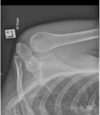

describe fracture

A

Extraarticular distal radius #